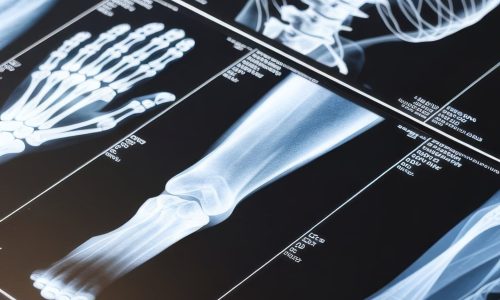

🏠 خدمة الأشعة المنزلية من عيادات بي.كير التخصصية – دلوقتي بخصم 25%!

📣 اطمن على صحتك بأمان وراحة في بيتك، من غير تنقل أو مجهود، مع خدمة أشعة منزلية متكاملة بأعلى جودة وتقارير معتمدة من استشاريين متخصصين.

🦴 أشعة عادية (X-Ray):

على الأطراف (الذراع – اليد – الرجل – الكتف – الركبة – الكاحل)

على العمود الفقري (رقبي – صدري – قطني – عجزي)

على مفاصل الجسم (الفخذ – الحوض – الكوع – الرسغ)

على الجمجمة والأسنان

على الصدر (القلب والرئة)

على البطن والحوض

على الفقرات لتقييم الخشونة أو الانزلاق الغضروفي

للكشف عن الكسور، الشروخ، أو التهابات العظام والمفاصل

حالات متابعة تركيب جبس أو تثبيت داخلي